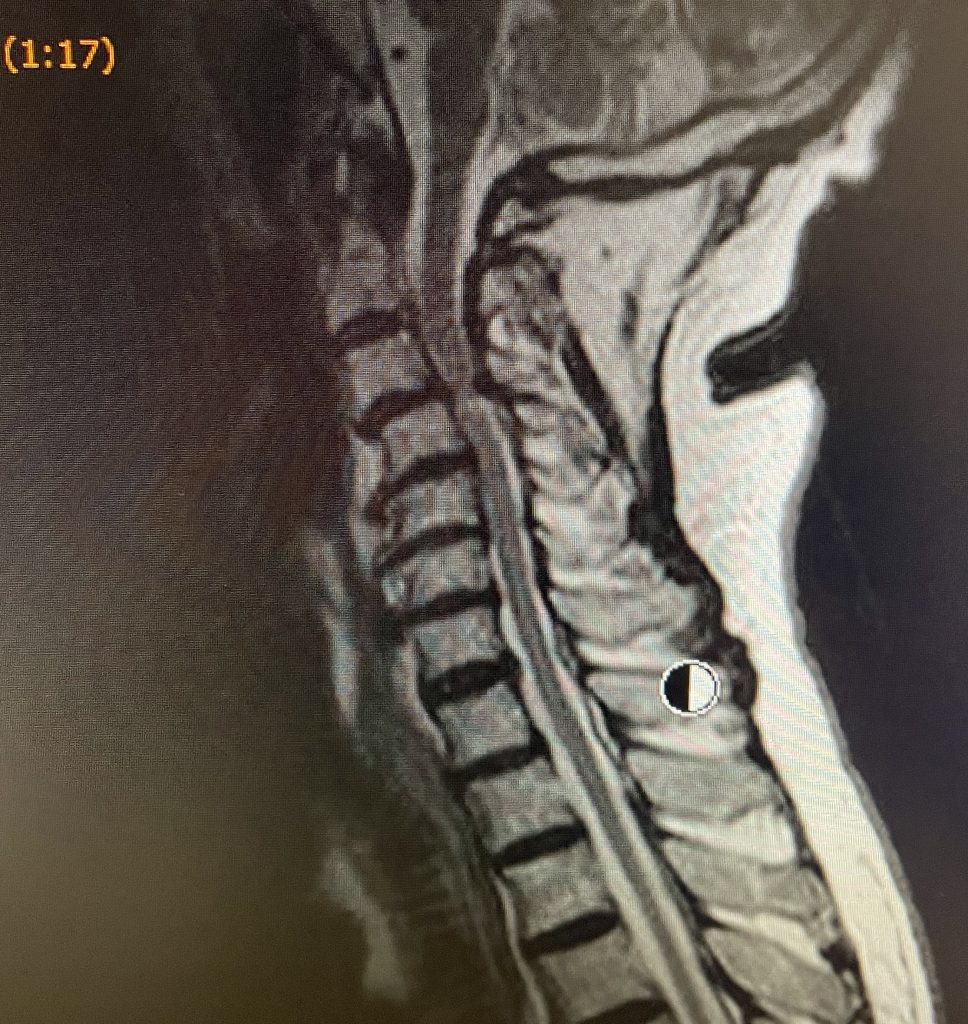

La mielopatia cervical es una lesión medular, resultante de la compresión crónica asociada a estenosis de canal cervical e inestabilidad discoligamentosa. En ocasiones hernias cervicales muy voluminosas pueden provocar síntomas muy similares.

La cirugía en casos de canal cervical estrecho y mielopatia cervical, consiste en descomprimir el espacio donde está el cordón medular comprimido, resecando discos dañados, elementos vertebrales (cuerpo, láminas…), para luego fijar y fusionar las vértebras entre sí.